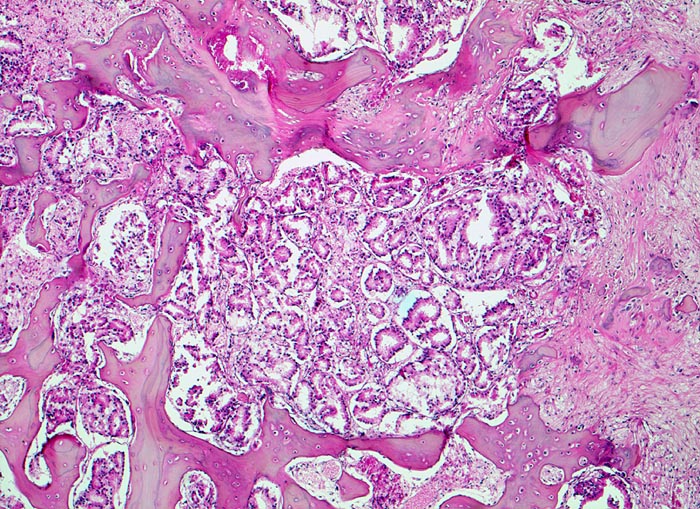

Da Adenokarzinome neben der Prostata in fast allen Organen vorkommenen, ist die Differentialdiagnose im HE Schnitt bei Nachweis einer Knochenmetastase eines Adenokarzinoms sehr breit. Die immunhistochemische Positivität der Tumorzellen für prostataspezifisches Antigen (PSA) spricht für eine Primärtumorherkunft aus der Prostata. Prostatakarzinome bilden typischerweise osteoplastische Knochenmetastasen. Die Knochenbildung erfolgt via Cytokine und Wachstumsfaktoren, die von den Tumorzellen gebildet werden (z.B. TGF-beta), durch Stimulation der Osteoblasten, wahrscheinlich bei gleichzeitiger lokaler Reduktion der Osteoklastenaktivität (RANK/RANKL/OPG-System). Die Stimulation von Osteoblasten führt zu einer vermehrten appositionellen Osteoidneubildung entlang vorhandener Trabekel mit nachfolgender Mineralisierung. Durch fortgeschrittene Knochenneubildung kommt es zu einer vollständigen Ummauerung grösserer Tumorareale, welche durch die verminderte Blutzufuhr nekrotisch werden. Vielfach lassen sich histologisch osteoplastische und osteolytische Anteile nachweisen. Immunhistochemisch lässt sich in den Metastasen oft Prostata spezifisches Antigen nachweisen (> 5342).

Morphologische Merkmale:

• Fehlen von blutbildendem Knochenmark.

• Infiltration des Knochemarks durch kleine dichtgepackte, kribriforme Strukturen ausbildende Karzinomdrüsen.

• Osteplastische Metastase: Faserknochenneubildung zwischen vorbestehenden Trabekeln.

• Anhand der Histologie kann lediglich die Diagnose einer Metastase eines Adenokarzinoms gestellt werden. Kleine, solide Verbände bildende Tumordrüsen und grosse Nukleolen sind typisch für ein Prostatakarzinom. Die Diagnose muss aber durch den Vergleich mit der Morphologie des Primärtumors oder eine Immunhistochemische Untersuchung (PSA, PSAP) bestätigt werden.